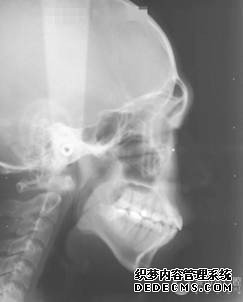

全景机侧位片